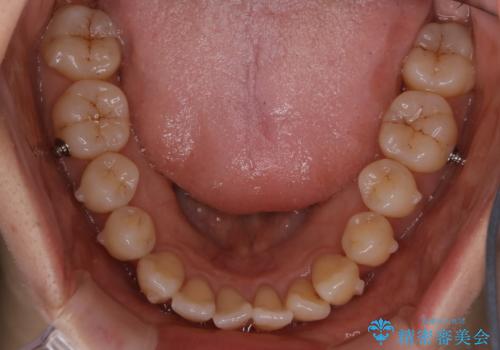

- 前歯のがたつきが気になるとご相談にいらした患者様です。矯正検査の結果、骨格的なズレが大きかったため当初の治療計画では外科矯正をご案内しました。ご本人が手術を望んでおらず、可能な限りの改善を目指すことを目標に治療を開始しました。

元々の骨格的なズレが大きかったため、当初は外科矯正をご提案していました。患者様の強いご希望により、非外科的な処置のみで可及的な改善を目指すことを目標に治療を行いました。以前よりもしっかり噛めるようになり、見た目も劇的に改善したことで大変ご満足いただけました。